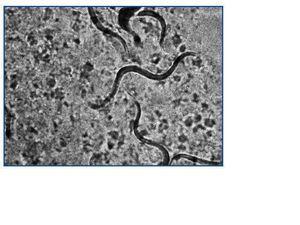

Varón de 55 años, en programa de DPCA crónica por insuficiencia renal secundaria a glomerulonefritis crónica. Recibió trasplante renal de donante cadáver en julio de 2005 e inmunosupresión con tacrolimus, micofenolato mofetil y prednisona; quedó con una función renal estable con creatinina en torno a 2,5 mg/dl. A los dos años del trasplante, presentó cuadro de diarrea persistente de 4-5 deposiciones al día, con pérdida de 2 kg de peso. El estudio microbiológico de heces detectó abundantes larvas de S. stercoralis (figura 1). La cifra de eosinófilos en sangre era normal (0,3 x 103/μl). El paciente residía en una localidad valenciana considerada como zona endémica de S. stercoralis. Se revisaron los antecedentes previos al trasplante, donde aparecieron episodios de urticaria y un asma leve que el paciente había tratado de forma esporádica con broncodilatadores. En las analíticas pretrasplante presentó de forma intermitente eosinofilia leve (1,0 x 103/ μl). Se inició tratamiento con tiabendazol a dosis de 1,5 g/12 horas (25 mg/kg/día) vía oral durante cinco días, repitiéndose el ciclo a los siete días por persistencia de la clínica. A los 14 días del inicio del tratamiento persistía la diarrea, con pérdida de 4 kg de peso y deterioro de la función renal, por lo que se ingresó para hidratación intravenosa. La muestra de heces obtenida durante el ingreso, así como la obtenida tras el segundo tratamiento con tiabendazol, fueron negativas para parásitos. El cuadro diarreico mejoró, con recuperación progresiva de la función renal hasta cifras de creatinina habituales. Una nueva muestra de estudio de parásitos en heces un mes más tarde fue negativa. En la actualidad, el paciente permanece asintomático, habiendo mejorado el cuadro urticariforme y el asma, con función renal estable. Se estudiaron los familiares convivientes, detectando en el hijo del paciente la presencia de S. stercoralis que se trató forma ambulatoria con tiabendazol.

El diagnóstico de S. stercoralis puede ser complejo. La única anomalía puede ser la eosinofilia, y en los pacientes trasplantados puede no estar presente. Por este motivo, ante un cuadro diarreico no autolimitado en un paciente trasplantado, debemos descartar complicaciones de posibles fármacos, como el micofenolato mofetil, especialmente si se asocia al efecto procinético del tacrolimus. Si además el estudio convencional en heces resulta negativo, debe contemplarse la posibilidad de que el cuadro diarreico sea secundario a una infección parasitaria. Para diagnosticar una parasitosis por S. stercoralis, puede ser necesario remitir varias muestras de heces frescas para la detección de posibles larvas6 (figura 1), ya que una muestra única no detecta la infección hasta en un 70% de los casos. La sensibilidad de la visión directa de heces frescas aumenta a un 50% si se remiten tres muestras y a un 100% si envían siete muestras7. Si se procede al cultivo de estas heces en agar-plata, como fue en nuestros dos casos, pueden objetivarse larvas infectivas (figura 2). También se dispone de un test de ELISA específico con alta sensibilidad y especificidad6, y un test de ELISA indirecto para detectar la presencia de anticuerpos IgG e IgM frente a S. stercoralis8. En pacientes inmunocomprometidos, este test de ELISA específico podría estar indicado cuando la sospecha de parasitación es alta y las muestras de heces son repetidamente negativas, pudiendo ayudar al establecimiento de un diagnóstico y tratamiento precoces. Los anticuerpos específicos IgG pueden permanecer positivos años después de finalizar el tratamiento antihelmíntico9.

Figura 1.